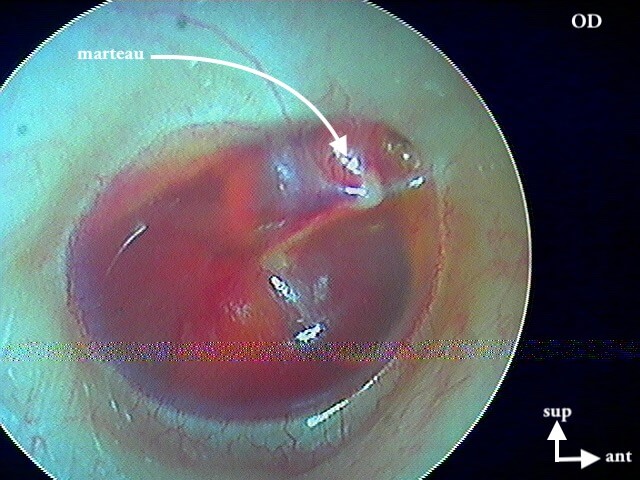

3/2 barotraumatique

– stade I : hyperhémie du manche du marteau et de la pars flaccida ;

– stade II : tympan rétracté, congestif, immobile

– stade III : aspect d'otite séromuqueuse

– stade IV : aspect otite séro-hémorragique, otohématome

– stade V : perforation

Ici des stades V perforés